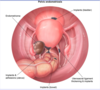

What is the likely diagnosis in a young woman that presents with chronic pelvic pain, especially with exercise, and a homogenous cystic ovarian mass on ultrasound?

Ovarian endometrioma (secondary to endometriosis)

endometriomas are also associated with infertility, which improves with surgical resection of the endometrioma